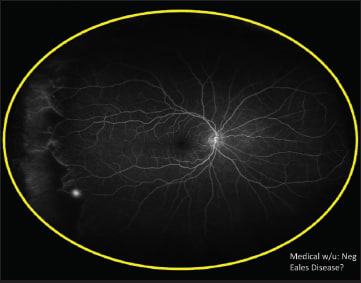

The second case Dr. Freund presented also used ultra widefield FA. This patient, a 55-year-old white woman, presented with what appeared to be posterior vitreous detachment–related symptoms, including the sudden onset of floaters related to a vitreous hemorrhage (Figure 1). The ultra widefield FA revealed instead that the problem arose from neovascularization related to peripheral nonperfusion; the fellow eye showed the same problem (Figures 2 and 3).

Figure 1. In this 55-year-old white woman, there was the appearance of a vitreous hemorrhage.

Figure 2. Ultra-widefield FA revealed neovascularization related to peripheral nonperfusion.